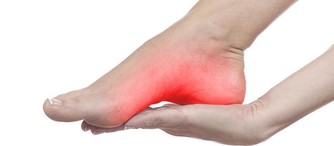

(1)有痛風病症的人群

五穀雜糧類食物,通常含有大量草酸,如果過量食用很有可能誘發痛風;

尤其豆類食物,少量食用就會導致尿酸增高,甚至還有可能誘發其他並發症。

因此,建議有痛風等病症的人群盡量少吃五穀雜糧類食物,以免導致痛風發作。